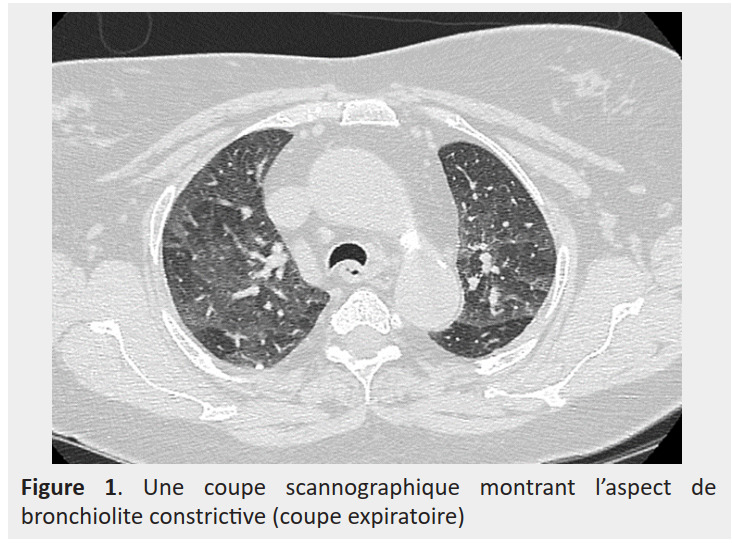

Results: During this period, we collected nine patients with an average age of 46. Dyspnea and cough were the most frequent symptoms. Chest computed tomography revealed ground-glass opacity in five cases, parenchymal condensations in three cases and crazy paving in three cases. The frequent risk factors were occupational exposure to a lipid in five cases and consumption of a lipid product in four cases. In terms of treatment, four patients underwent occupational reclassification and a declaration of occupational disease. Systemic corticotherapy was indicated in six patients.